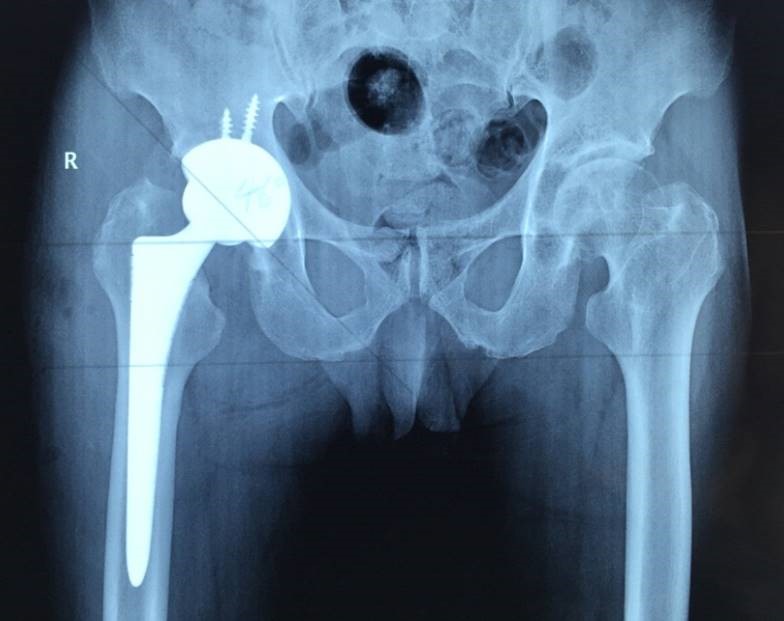

第 44 届世界骨科大会(OWC/SICOT)在塞尔维亚的贝尔格莱德隆重举行。SICOT 作为国际上久负盛名的矫形与创伤学术组织,于1929 年在浪漫之都法国巴黎诞生,如今其总部坐落于比利时布鲁塞尔。该组织始终秉持着推动骨与创伤学科不断进步的使命,致力于提升全球患者的医疗水平,在…